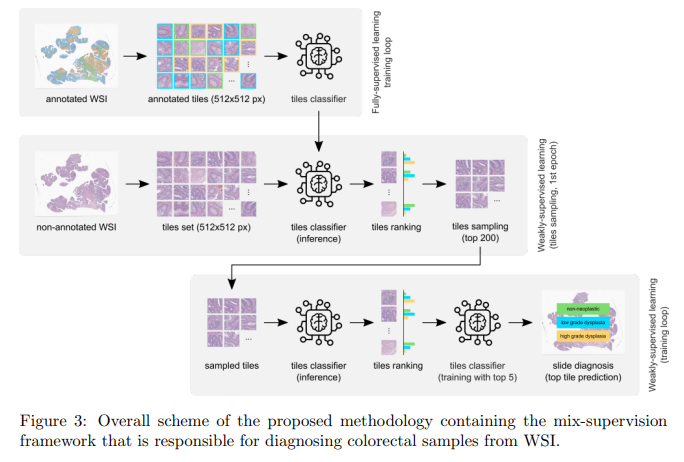

结直肠癌检测的全流程开发与验证

在过去的几年里,人工智能(AI)和数字病理学的整合一直在增加。如今,应用深度学习(DL)方法从整个影像图像(WSI)中诊断癌症,引起很多研究小组的兴趣。然而,这些系统的发展受到了无数限制,包括缺乏训练样本、缩放困难、DL方法的不透明性,以及更重要的是缺乏临床验证。

因此,我们提出了一个专门为结直肠样本诊断设计的系统。这样一个系统的构建包括四个阶段。(1) 仔细的数据收集和注释过程,这导致了最大的WSI结直肠样本数据集之一;(2) 设计一个可解释的混合监督方案,以利用病理学家通过空间注释引入的领域知识;(3) 根据每个tile的预期严重程度开发一个有效的采样方法,这将计算成本降低了近6倍;(4) 创建一个原型系统,整合模型的全部特征,在临床实践中进行评估。

所提出的方法在四个独立的测试集中进行了评估,其中两个是外部的,完全独立的。在其中最大的测试集上,提出的方法达到了93.44%的准确率。结直肠样本的DL研究,距离完全融入临床实践又近了几步。